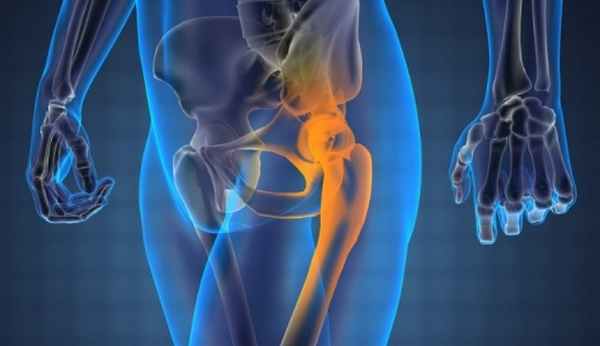

>>>Опухоль крыла правой подвздошной кости, диагностированная четыре года назад, обнаруженная на рентгеновском снимке, сделанном в рамках медосмотра подвздошной массы. Появление болей при пальпации и увеличение размера опухоли.

>>>Рентгенография: Экзостоз на широкой ножке. Тонкие очаги обызвествления вокруг поражения, но не всплошную, подозрительные.

КТ: контур периферического кортикального слоя не прерывается на границе с кортикальным слоем подвздошной кости. Хорошо различимая трабекулярная структура указывает на остеогенный экзостоз.

Свидетельствует о наличии хрящевого обызвествления, захватывающего, по-видимому, соседние мягкие ткани.

МРТ: чётко видимая хрящевая шапочка, имеющая геперинтенсивный сигнал на T2 (DP)-ВИ и изоинтенсивный сигнал на Т1-ВИ, неправильной формы и очень плотная (23 мм), принимающая дольчатый вид, вызывающая подозрение на саркоматозную дегенерацию. Периферическое повышение сигнала после инъекции.

Хондросаркома на почве остеогенного экзостоза